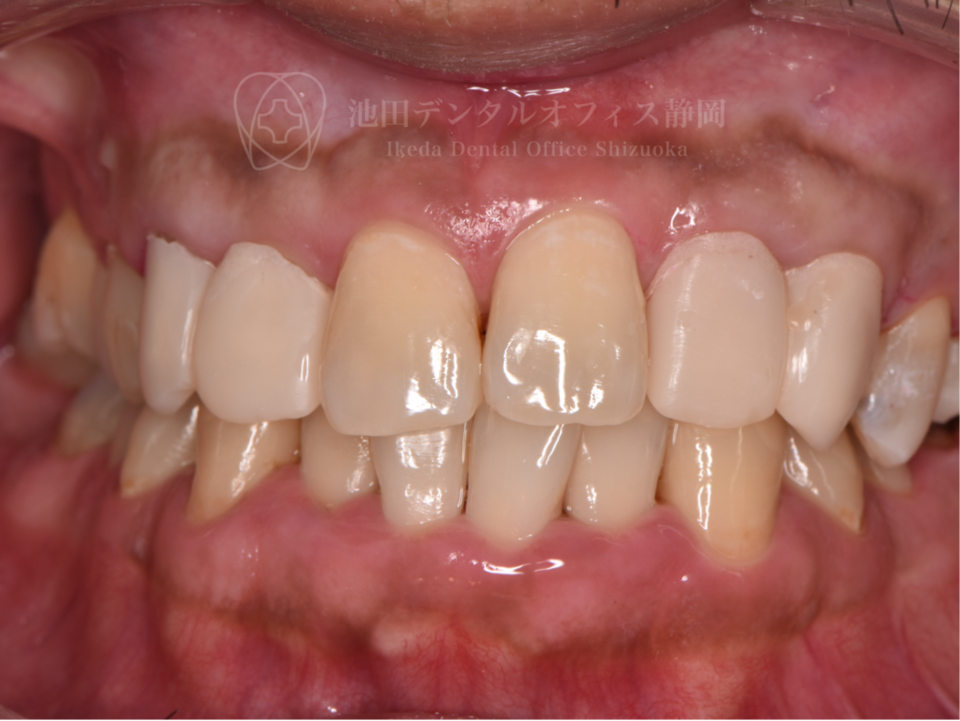

長年歯科へ通院できず、状態が悪化したため「歯医者に行くのも恥ずかしい」と悩んでいた患者さんです。歯の状態が悪く抜かなければいけない歯もありましたが、インプラント治療をしたくないとの希望があったため歯の移植などを行いできる限りご自身の歯を残しました。

歯科に対する恐怖心が強く、ご本人への負担が大きい治療は麻酔科の先生と連携して静脈内鎮静法で治療を行いました。移植後のセラミック治療により見た目と噛み合わせを改善しています。